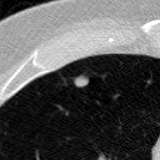

The current study focuses on lung nodule retrieval from a database of CT scans, where patches taken from CT slices of pulmonary nodules are to be mapped into an embedding. LIDC-IDRI [5] is a dataset of thoracic CT scans of 1,010 patients. All the scans were annotated by up to four radiologists, where each one identified, segmented and evaluated separately the lung nodules of a diameter above . Their evaluation also included ratings for a set of 9 characteristics: Subtlety, Internal structure, Calcification, Sphericity, Margin, Lobulation, Spiculation, Texture and Malignancy. The rating system was based on a discrete score of 1-5. Four examples of nodule patches are illustrated in Figure 2: 2 benign (a, b) and 2 malignant (c, d). A rounded vector of the mean rating is bellow each nodule, with the characteristics ordered according to the listing above. The most prominent difference between a and b is the calcification: 3 (solid) and 6 (absent) accordingly. d compared to c has a more defined margin, is more lobulated, but less spiculated. The malignancy score is used to define malignancy classes: score of 1-2 is benign, score of 3 is unknown, and a score of 4-5 is malignant.

(a) Benign

3, 1, 3, 3, 4, 3, 1, 5, 1

(b) Benign

3, 1, 6, 5, 5, 1, 1, 5, 2

(c) Malignant

5, 1, 6, 3, 3, 4, 1, 5, 5

(d) Malignant

4, 1, 6, 3, 4, 2, 2, 5, 4